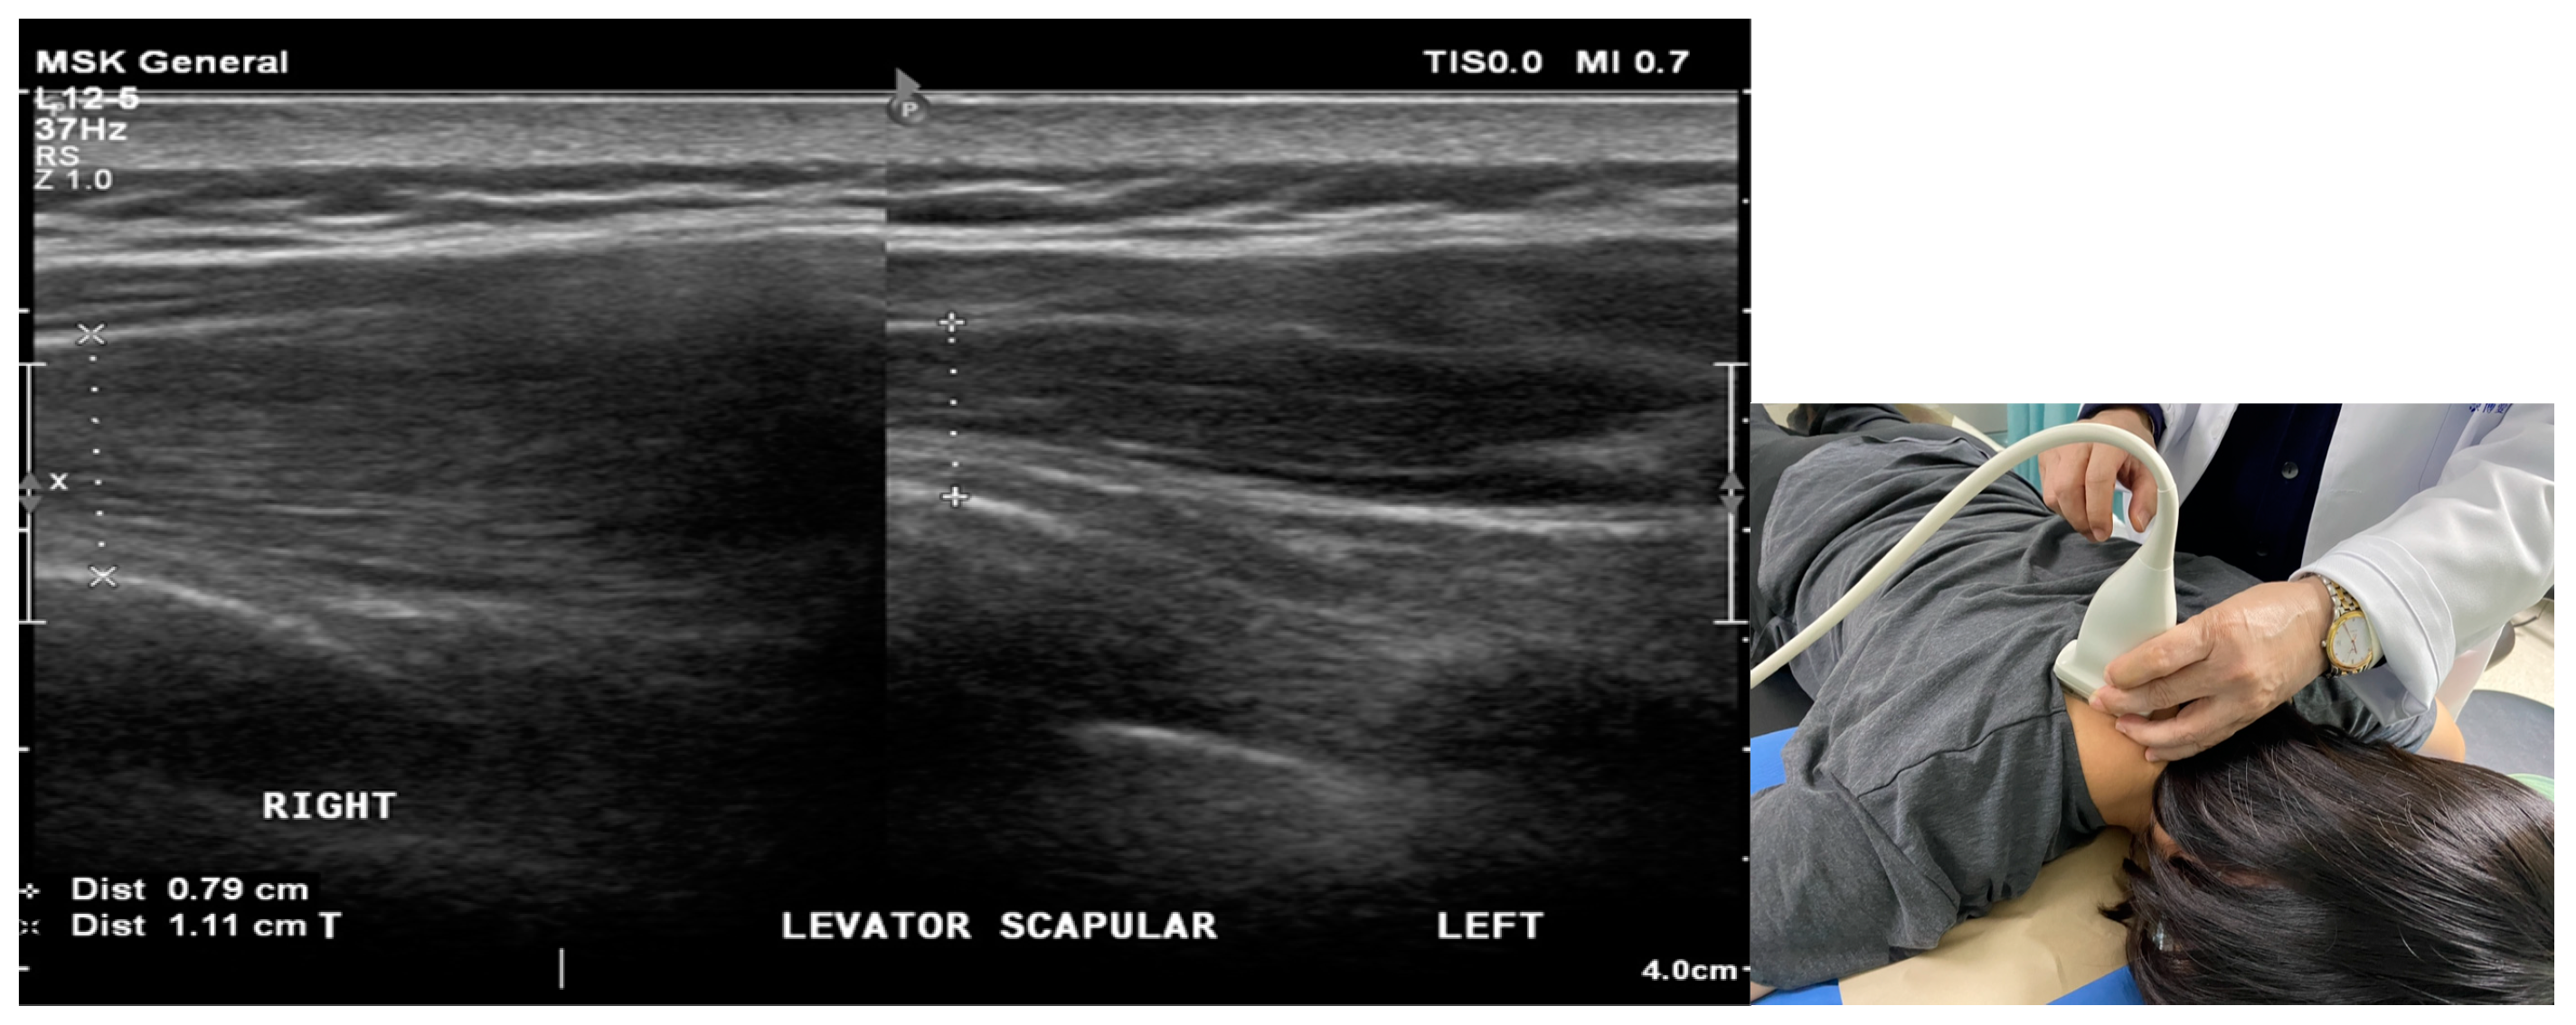

2.2. Ultrasound Examination